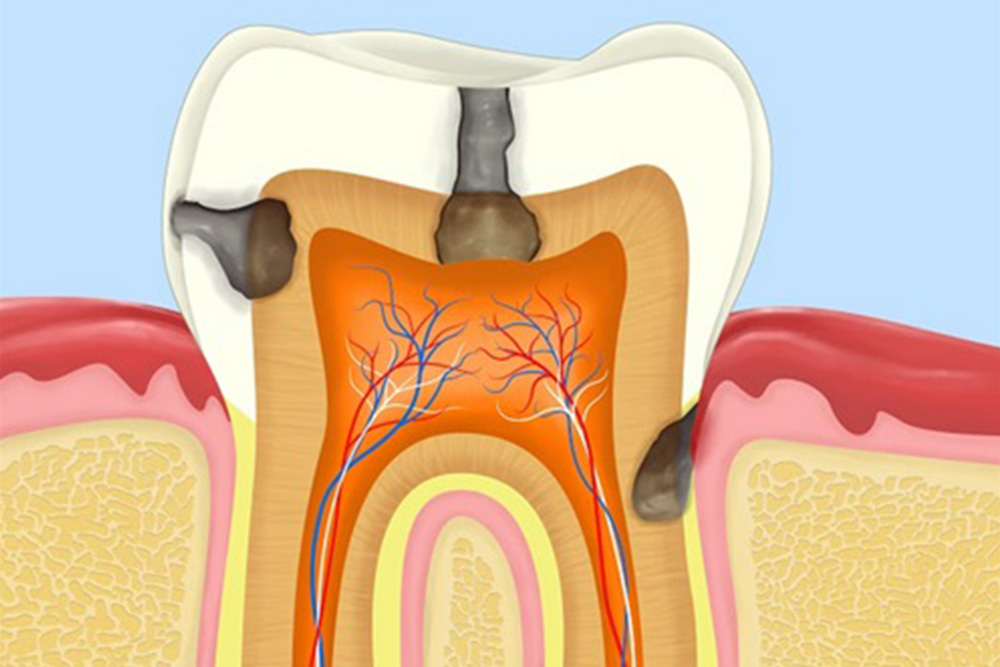

虫歯・歯周病になっている

親知らずはお口の最も奥に生えるため、歯ブラシが届きにくく、虫歯や歯周病のリスクが高くなります。治療を行っても十分なケアが難しい場合には、再発を繰り返すだけでなく、周囲の歯にも悪影響を及ぼす可能性があります。そのため、親知らずが虫歯や歯周病になっている場合には、抜歯を検討・推奨することがあります。